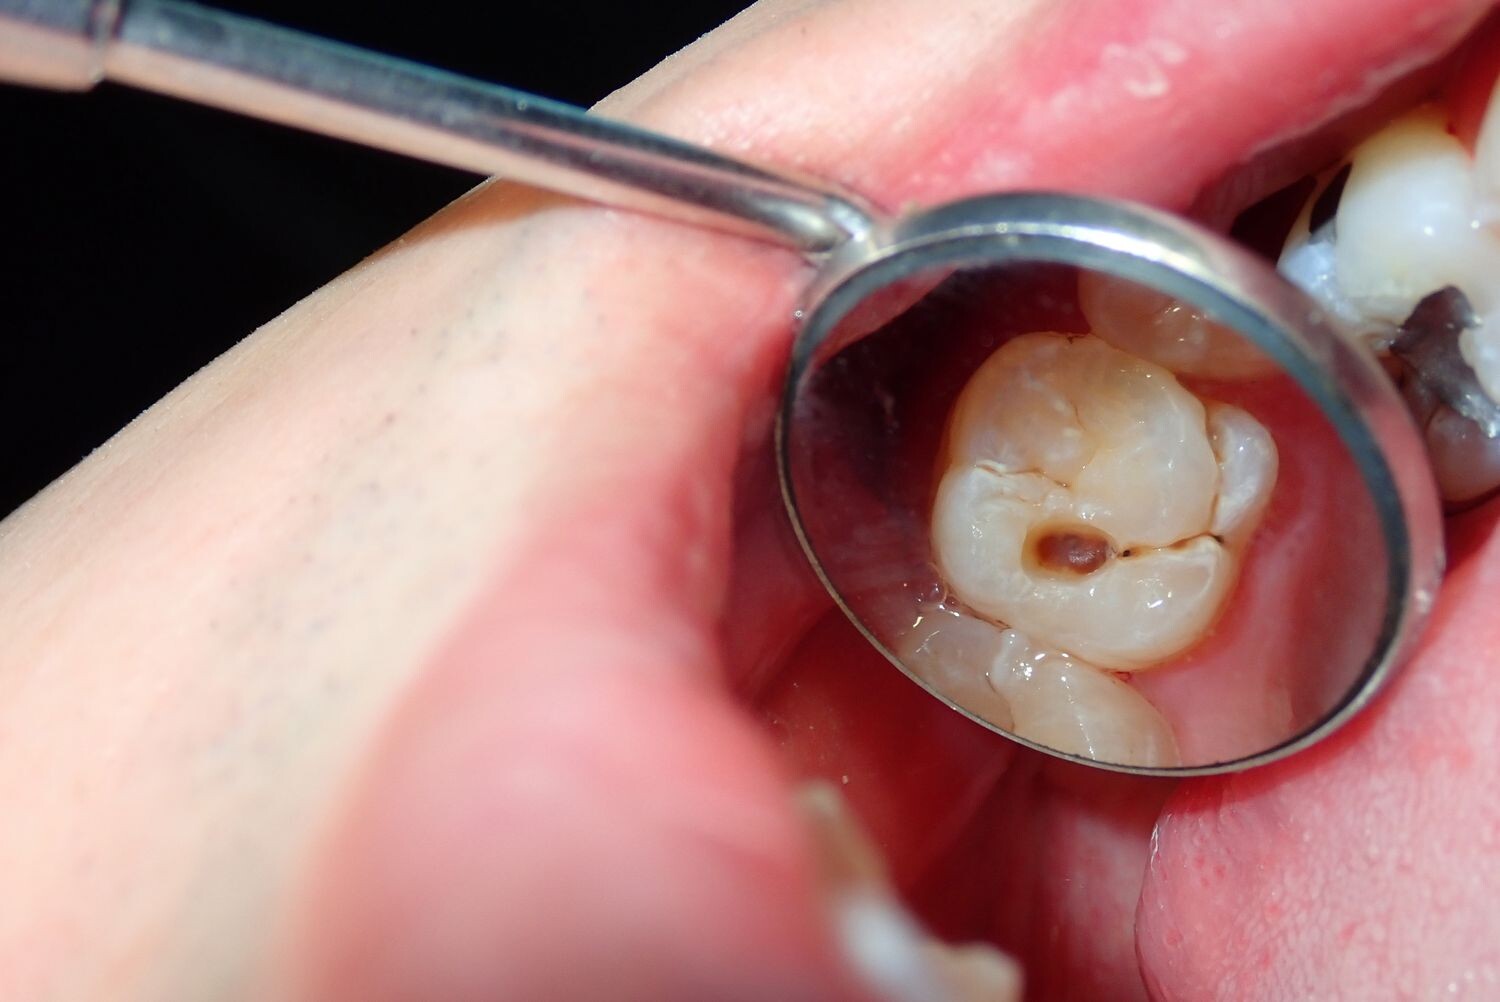

Cavities are pretty common. As the National Institutes of Health points out, the only condition more common than a cavity is the common cold. If you've never experienced tooth decay, you might wonder, "What does a cavity feel like?" The answer depends on the stage of the cavity and what foods you eat. Some foods, such as sweets, might trigger the pain of a cavity more than others.

Signs of a Cavity

What does a cavity feel like? In the earliest stages, the answer might be nothing. There are no nerves in your tooth enamel, so when the decay is in that layer, you likely won't feel a thing. Once the decay has progressed enough to reach the softer tissues inside the tooth, where the dentin and nerves are, you might notice signs of a cavity. Your teeth might feel sensitive and you could feel some pain, especially after eating sweets, hot foods or cold foods. The pain can be fairly mild or sharp and intense. Some people with cavities also feel pain when biting down.

Depending on the size of the cavity, you may be able to see evidence of it in your mouth. Cavities sometimes create visible holes in the teeth. They can also create stains that are black, brown or white on the surface of the tooth.